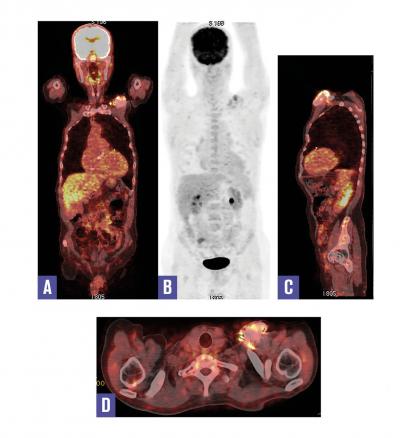

Cet homme de 71 ans, qui avait bénéficié d’un remplacement valvulaire aortique il y a 2 ans et de la pose d’un défibrillateur automatique implantable il y a 8 mois, consultait pour une fièvre prolongée. L’auscultation cardiaque notait un souffle au foyer aortique. La protéine C-réactive et la procalcitonine étaient élevées, les hémocultures étaient positives à Streptococcus aureus ; l’échographie transœsophagienne ne montrait pas de végétation sur la valve prothétique. Une tomographie par émission de positons couplée à la tomo- densitométrie au 18fluorodésoxyglucose (TEP-TDM au 18F-FDG) était réalisée, elle était négative au niveau cardiaque ; en revanche elle montrait un hypermétabolisme pathologique au pourtour du boîtier du défibrillateur implanté au niveau prépectoral gauche. Ce dernier était retiré et l’examen bactériologique confirmait la présence de Streptococcus aureus.